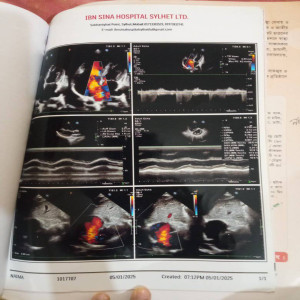

#250909I: জটিল কিডনি সমস্যায় আক্রান্ত শহিদুল ইসলাম চিকিৎসার জন্য সাহায্য চেয়েছেন, গ্রাম: মহব্বতপুর, জেলা: দিনাজপুর।